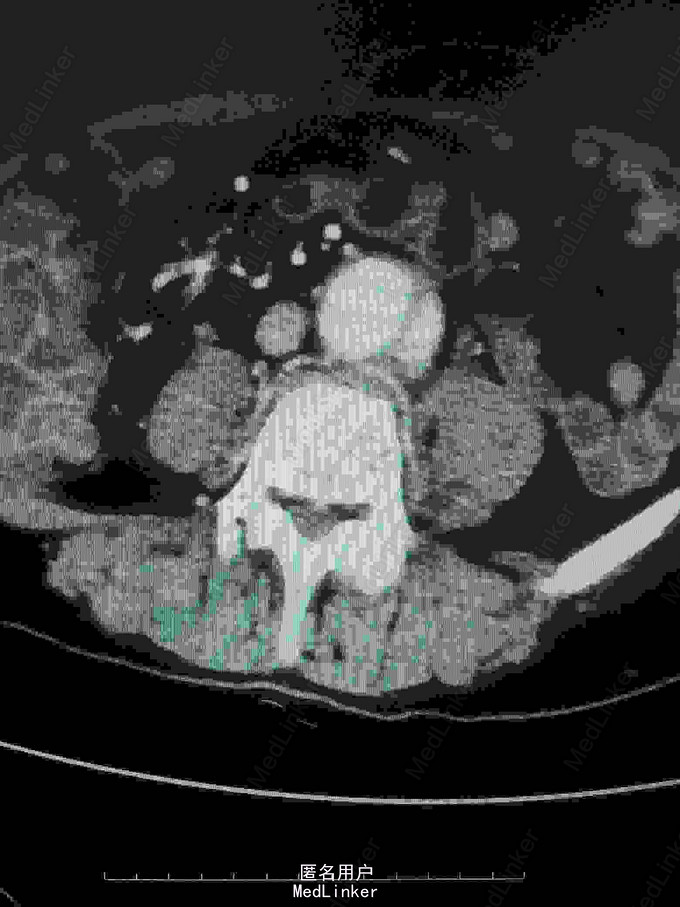

主诉:腰腹痛7月,加重一周。 病史:七月前发热后开始出现腰腹痛,呈持续性撕裂样痛,伴腹胀,症状反复。一周前腹痛症状加重。

体查:下腹部可触及搏动性包块。 辅助检查:腹部CT:腹主动脉假性动脉瘤并血栓形成,腰5椎体受侵蚀。血培养:沙门氏菌。

诊断:沙门氏菌感染性腹主动脉假性动脉瘤 处理:急诊行腹主动脉瘤切除人工血管置换术,术后予美罗培南抗感染8周,续以左氧氟沙星口服。